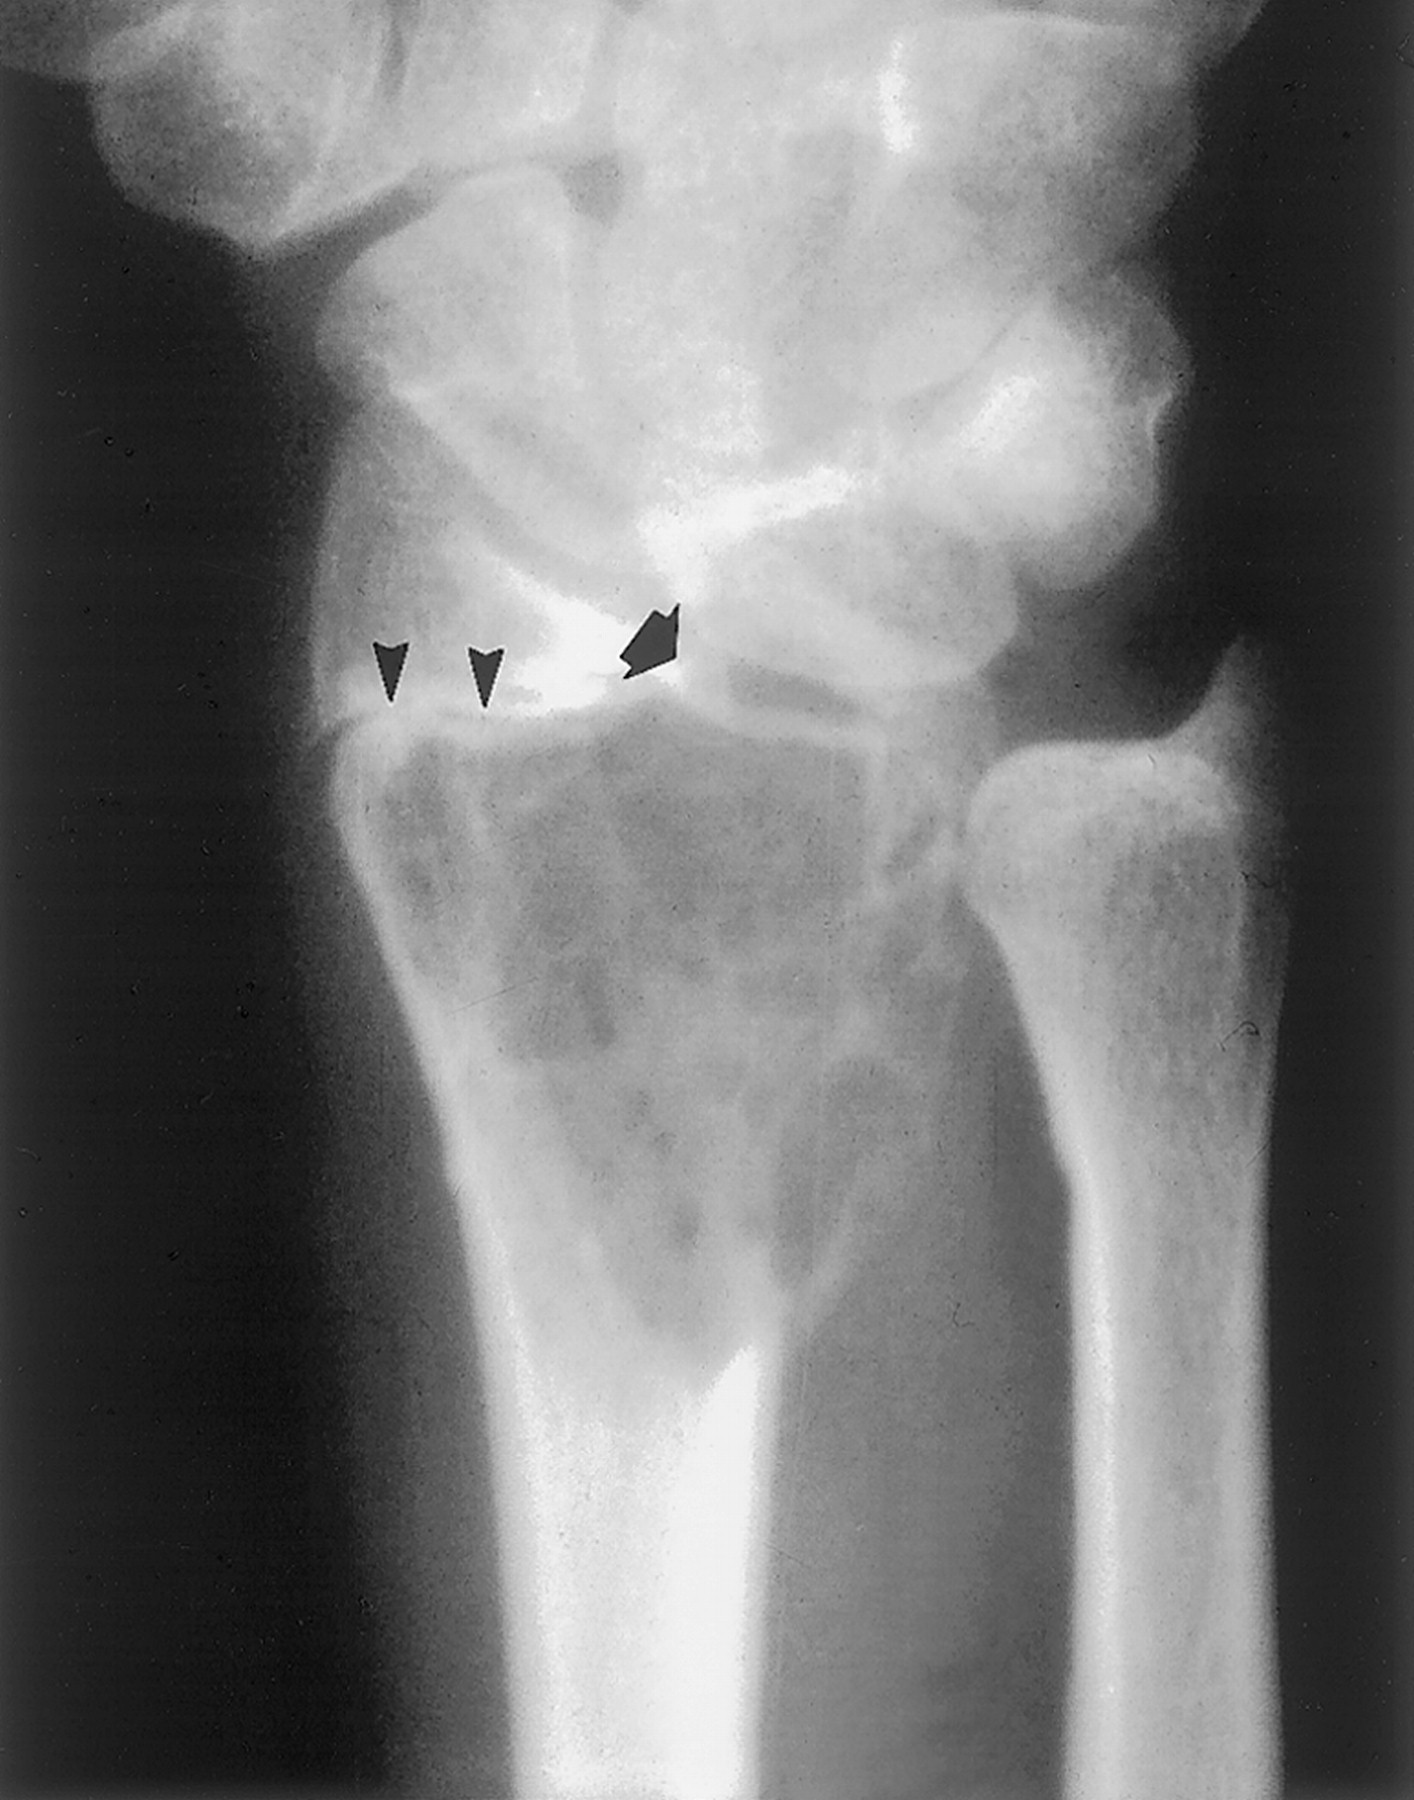

Злокачественная гигантоклеточная  опухоль возникает из доброкачественной (частота 10-20%). После операции возможно появление рецидива опухоли.

Гигантоклеточная опухоль